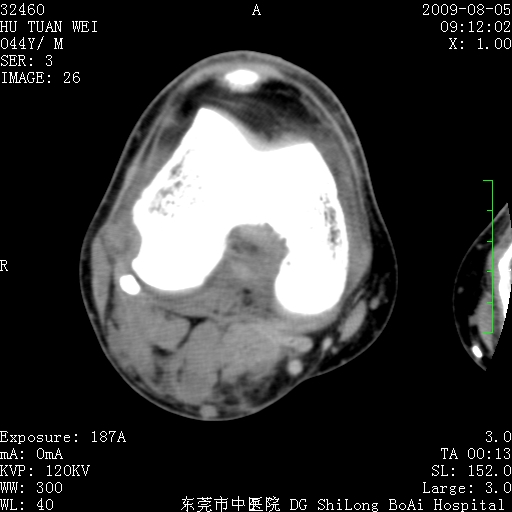

中年男性,膝韧带损伤术前检查!其他病史不清粗,不是我接手病人、且出院了!

1、股骨下段囊状膨胀性病变,边缘硬化明显,内多个残留骨棘呈多房型改变,囊腔密度较高无钙化,膝关节滑膜囊增厚,密度增高,关节腔少量积液。考虑:邻关节囊肿、退变性囊肿(软骨下囊肿)、着色性绒毛结节性滑膜炎、abc、骨巨、良性纤维组织细胞瘤等鉴。虽然年龄偏大,部位于骨端,但有外伤史,本人还是倾向于动脉瘤样骨囊肿(abc)可能性大。邻关节囊肿及软骨下囊肿次之考虑。

2、胫骨髁间棘撕脱骨折,交叉韧带损伤可能;

3、关节退行性改变。

病理结果:色素沉着绒毛结节性滑膜炎

感谢反馈病理结果!本病为慢性关节病变。以关节滑膜高度增生、绒毛结节形成伴含铁血黄素趁着为特点。病因:有炎症、肿瘤、外伤关节出血、代谢障碍、变态反应及感染等学说。增强扫描呈关节腔内单个或多个强化的软组织结节影或滑膜不规则增厚伴关节积液为本病的特征性表现。